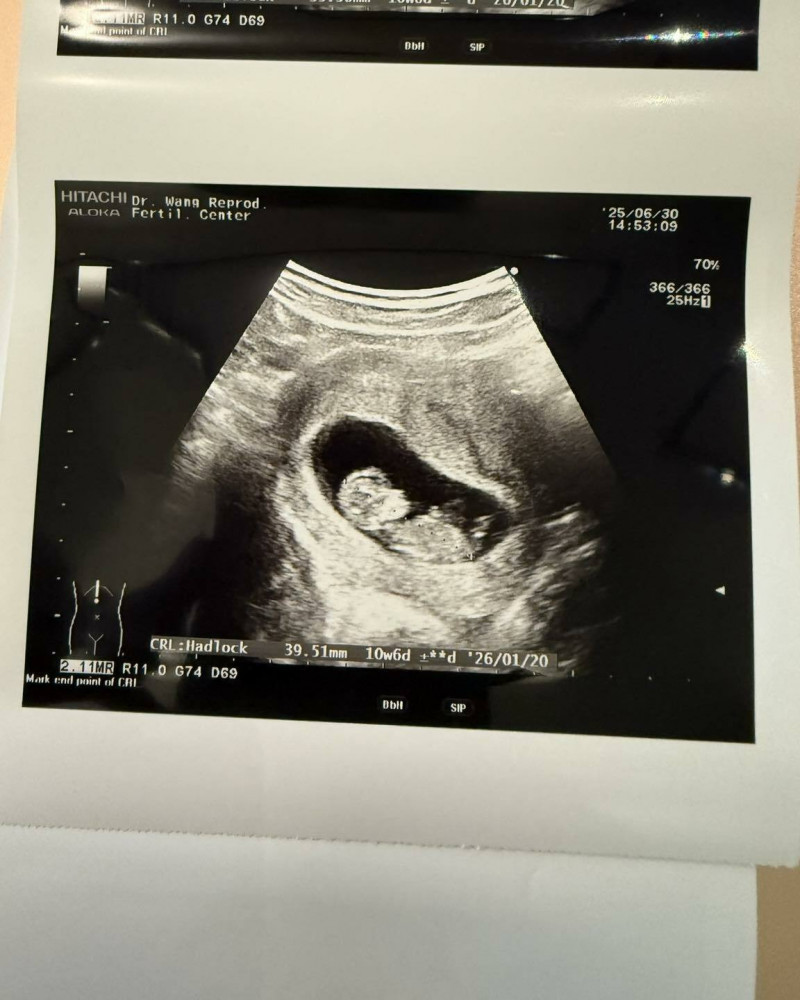

嚴爵在父親節秀出超音波照片,老婆終於懷孕了。(翻攝自臉書)

對於老婆這次能順利懷孕,嚴爵再次感謝醫生這一路來的幫助,「兩年來一路陪著我們從失敗走到成功,溫柔又專業,陪我們走到10週拿到『畢業證書』,真的很感動!」嚴爵也不忘關心老婆:「最辛苦的還是廢貓太太啦,每次療程都像在過關打怪,身心都超不容易,謝謝她願意這樣努力,也謝謝肚子裡的寶寶乖乖長大。」